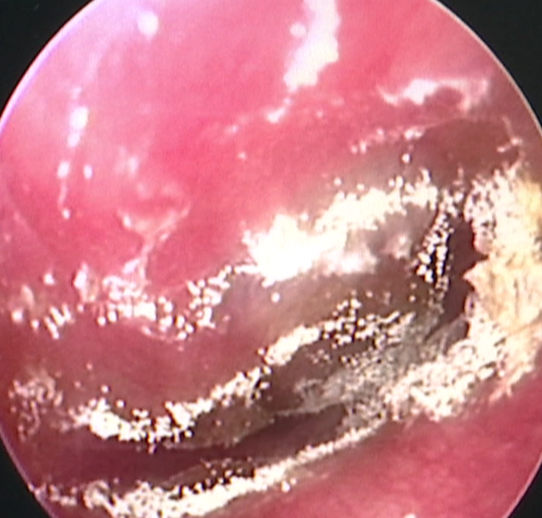

俗话说,“掏耳朵一时爽,一直掏一直爽”。市区的李先生平时也喜欢掏掏耳朵。然而,近期他觉得耳朵反复瘙痒、流脓、听力下降,听声音还闷闷的,就到医院做了耳内镜。不看不要紧,一看发现,李先生外耳道不仅水肿、有脓性分泌物,表面竟还长出了黑色的霉菌丝!

九〇九医院五官科副主任医师伍小琴医生诊断,李先生患上了真菌性外耳道炎,又称霉菌性外耳道炎。